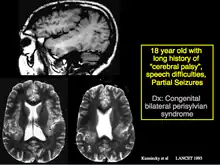

He was one of the first to recognize and prove that mesial temporal sclerosis, a common cause for difficulty in controlling temporal lobe epilepsy, can be identified with MRI scans. He also described the Kuzniecky Syndrome in 1991, also known as perisylvian polymicrogyria. The syndrome is characterized by seizures, cognitive abnormalities, and a peculiar inability to use the mouth and tongue muscles. This syndrome is recognized by as a specific malformation of the brain.

Kuzniecky described the Kuzniecky Syndrome in 1991, also known as perisylvian polymicrogyria.[6] The syndrome is characterized by seizures, cognitive abnormalities, and a peculiar inability to use the mouth and tongue muscles. This syndrome is recognized by as a specific malformation of the brain.[7]

MRI showing the abnormal infolding of the perisylvian region typical of this syndrome. The abnormality is due to polymicrogyria.